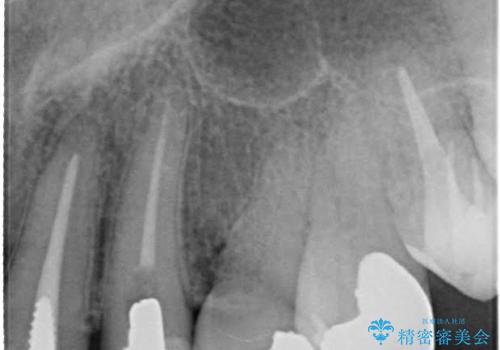

- 仮歯の製作、古い土台(メタルコア)の除去まで行い、根管治療は専門医に依頼

→根管治療終了後、ファイバーコアを築造し、新しいセラミックブリッジを製作した。

一見きれいにはいっているセラミックも、はずして中の状態をみるとひどいことが多い。これは、中の土台の状態や処理のクオリティは、短期的には問題を起こしづらく、患者さんには見えない部分だからです。